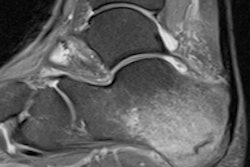

Image shows fiber tractography of the biceps femoris muscle at the three study time points for one marathoner. The fiber tracts are color-coded to show the changes in mean diffusivity. Image courtesy of Radiology.Tensor eigenvalues and mean diffusivity remained significantly elevated in the biceps femoris muscle three weeks after the run.